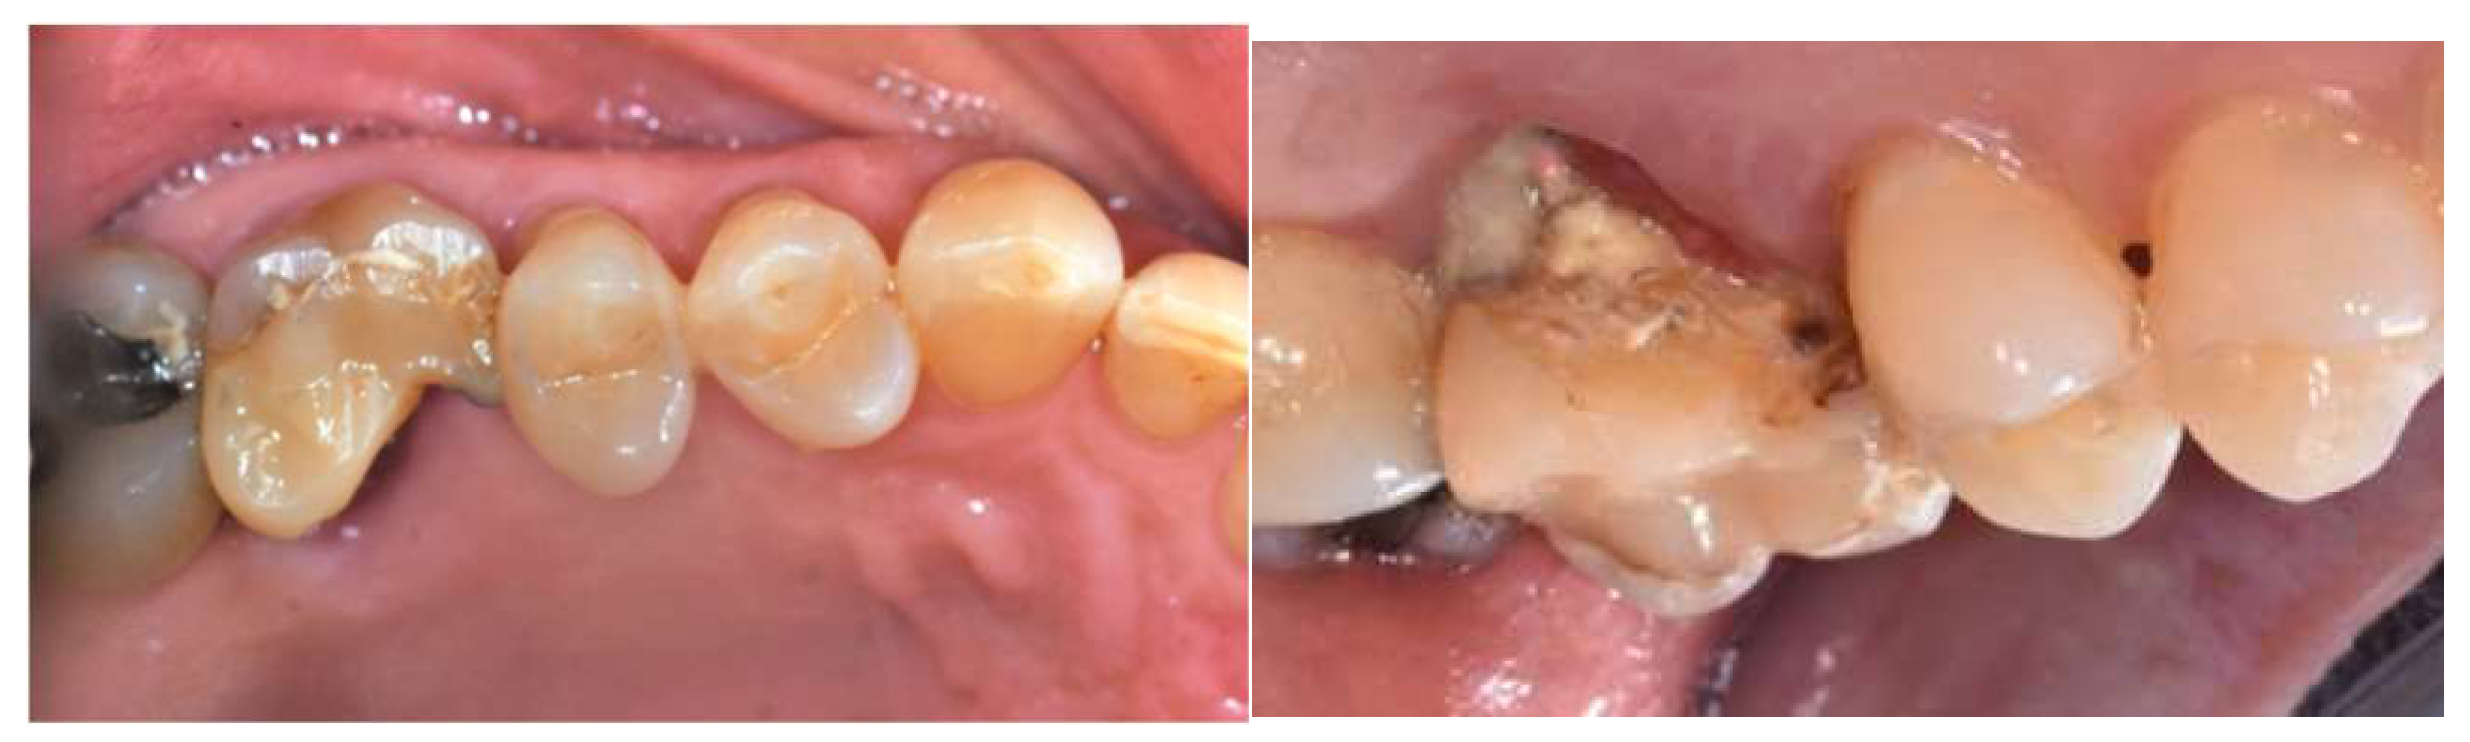

Occlusal and lateral endoral pictures of the elements to be extracted were taken before starting the surgery session (Figure 1 and Figure 2).

Figure 1, 2. Occlusal and lateral view of one of the dental element to be extracted (16).